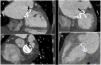

Prosthetic valve obstruction is a rare but potentially lethal complication. The most frequent causes are thrombus and pannus formation, in the absence of infectious data. Diagnosis is not always easy using cardiac CT scanning and in 46%–85% of cases thrombus and pannus coexist, complicating the diagnosis. A rapid diagnosis is essential to avoid a fatal outcome of this pathology whose mortality, despite correct treatment, is high.